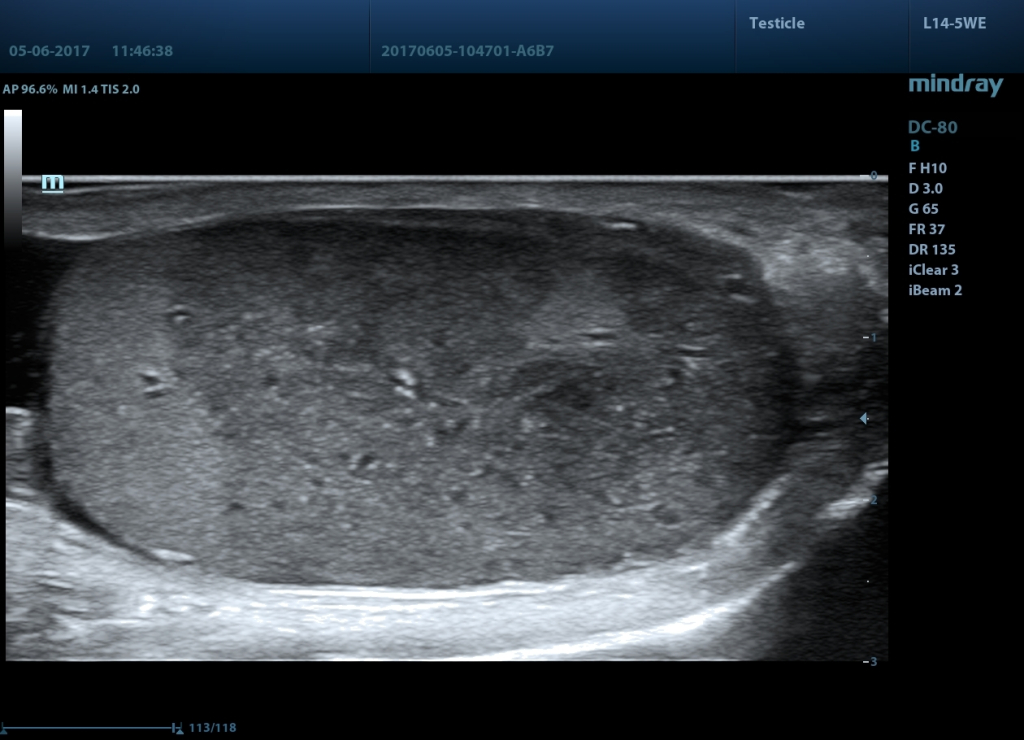

Галерея изображений:

3 - Инфаркт, датчик L14-5WE